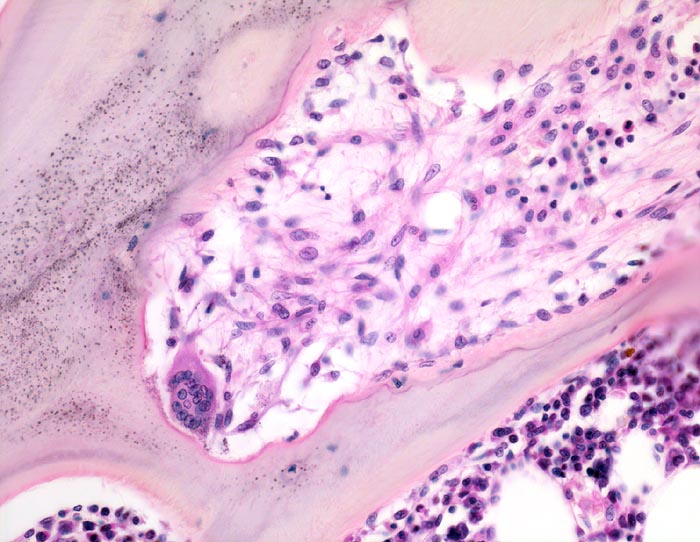

• Dünne Spongiosabälkchen mit herdförmiger peritrabekulärer Fibrose.

• Vermehrte Osteoklastentätigkeit: Spongiosabälkchen mit tiefen Resorptionslakunen, welche die Bälkchen z.T. tunnelartig aushöhlen.

• Die Resorptionslakune ist aufgefüllt mit lockerem Bindegewebe gebildet von Fibroblasten.